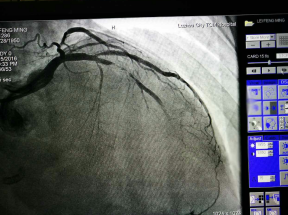

為求明確診斷及進(jìn)一步治療,周阿姨慕名來到了我院心血管內(nèi)科住院診治。經(jīng)冠狀動(dòng)脈造影檢查,發(fā)現(xiàn)原來植入的支架發(fā)生了99%的狹窄,即支架內(nèi)再狹窄,這就是導(dǎo)致她目前再次出現(xiàn)活動(dòng)后胸悶胸痛的根本原因。

術(shù)前